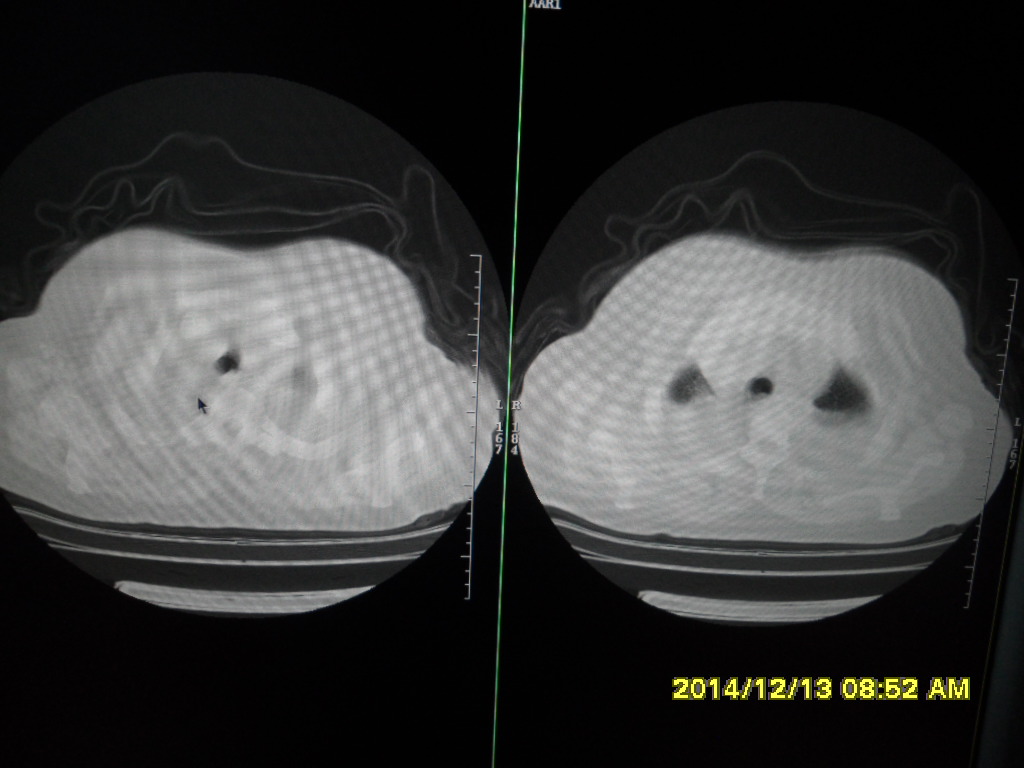

CT49563:左肺门长东西了?

双侧胸腔积液 肺感染